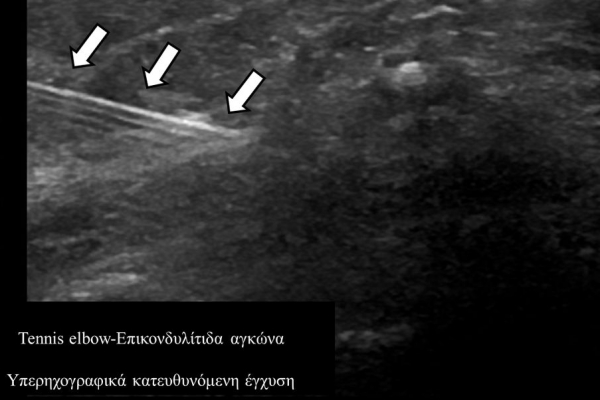

Υπό συνεχή υπερηχογραφική παρακολούθηση είναι δυνατόν να πραγματοποιηθούν κατευθυνόμενες εγχύσεις σε ορθοπαιδικές και ρευματολογικές παθήσεις. Αρχικά εντοπίζεται η παθολογική περιοχή και στη συνέχεια εξετάζεται η βέλτιστη οδός προσπέλασης. Ακολούθως γίνεται υπό άμεση και συνεχή υπερηχογραφική παρακολούθηση οι απαραίτητοι χειρισμοί και έγχυση φαρμάκων ακριβώς στη θέση της βλάβης.

Οι διαγνωστικές-θεραπευτικές εγχύσεις είναι δυνατόν να γίνουν σε μια πλειάδα μυοσκελετικών-ρευματολογικών παθήσεων όπως:

σε επικονδυλίτιδα αγκώνα